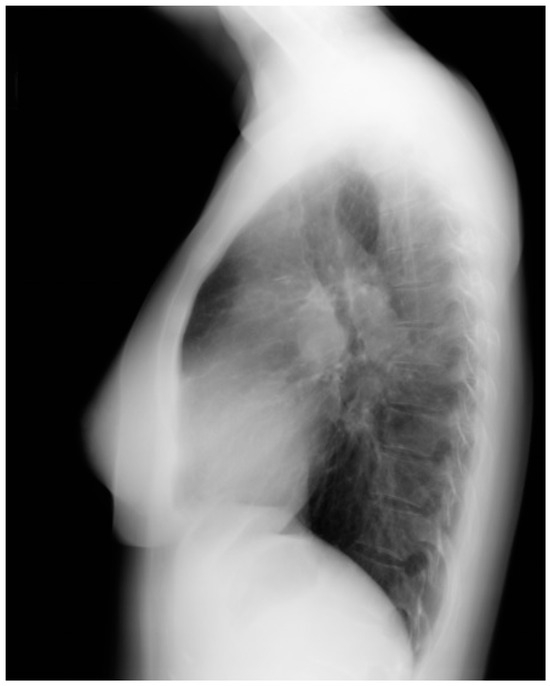

Figure 21.

Lateral chest X-ray of Marfan syndrome: this chest X-ray was done on the same 24-year-old female above. It shows the dorsal kyphosis and pectus carinatum (also known as pigeon chest). The ascending, arch, and descending aorta were markedly dilated. Additional imaging measured the minimum thoracic aortic diameter to be 6 cm. She went on to have a mechanical aortic valve replacement, followed by aortic root and ascending aortic replacement via median sternotomy, and then descending aortic replacement via left lateral thoracotomy. A few years later she required an extensive abdominal aortic replacement with multiple arterial anastomoses to vital organs supplied by the abdominal aorta. She was followed for 30 years after her first diagnosis of MFS and her first aortic operation and remained NYHA functional class 1–2. Suspicion of the diagnosis of MFS in an asymptomatic patient that leads to a CXR is an important first step in the optimal care of MFS.